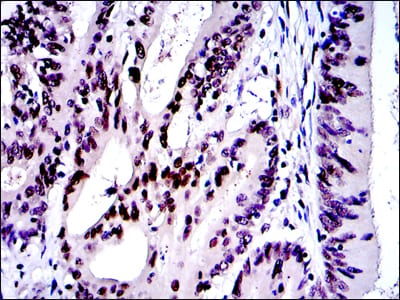

Immunohistochemical analysis of paraffin-embedded human cervical cancer tissues using c-Jun mouse mAb with DAB staining.

Immunohistochemical analysis of paraffin-embedded human colon cancer tissues using c-Jun mouse mAb with DAB staining.